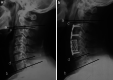

The purpose of this article is to compare the outcomes of three different anterior approaches for three-level cervical spondylosis. The records of 120 patients who underwent anterior approaches because of three-level cervical spondylosis between 2006 and 2008 were reviewed. Based on the type of surgery, the patients were divided into three groups: Group 1 was three-level anterior cervical discectomy and fusion (ACDF); Group 2 anterior cervical hybrid decompression and fusion (ACHDF, combination of ACDF and ACCF); and Group 3 two-level anterior cervical corpectomy and fusion (ACCF). The clinical outcomes including blood loss, operation time, complications, Japanese Orthopedic Association (JOA) scores, C2-C7 angle, segmental angle, and fusion rate were compared. There were no significant differences in JOA improvement and fusion rate among three groups. However, in terms of segmental angle and C2-C7 angle improvement, Group 2 was superior to Group 3 and inferior to Group 1 (all P < 0.01). Group 2 was less in operation time than Group 3 (P < 0.01) and more than Group 1 (P < 0.01). Group 3 had more blood loss than Group 1 and Group 2 (all P < 0.01) and had higher complication rate than Group 1 (P < 0.05). No significant differences in blood loss and complication rate were observed between Group 1 and Group 2 (P > 0.05). ACDF was superior in most outcomes to ACCF and ACHDF. If the compressive pathology could be resolved by discectomy, ACDF should be the treatment of choice. ACHDF was an ideal alternative procedure to ACDF if retro-vertebral pathology existed. ACCF was the last choice considered.